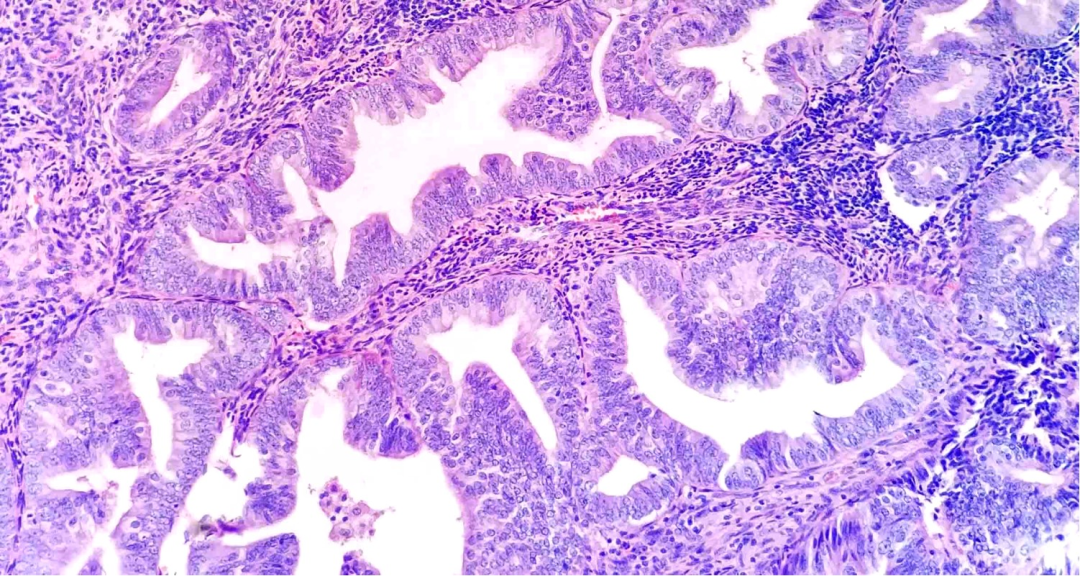

·子宫内膜非典型增生

又名子宫内膜样上皮内瘤变,表现为子宫内膜的腺体数量增加,排列拥挤,同时伴细胞非典型。部分病例表现为局部内膜增厚 (可呈息肉样),或弥漫增厚,部分病例大体表现不明显

结构: 复杂型增生:腺体排列变得拥挤,腺体/间质比例>3:1,腺体轮廓不规则,分支更加复杂,可向腺腔内形成乳头状折叠,腺体呈“背靠背”样排列拥挤(仅有少量间质分隔),结构上明显不同于邻近子宫内膜 (“地图状分布,与周围界清”)[特征],需排除基底部腺体、息肉、子宫内膜周期不同步等,缺乏:腺体融合,呈筛状或迷路状 (癌变特征)

细胞: 伴有非典型:腺上皮细胞复层化,极性消失,腺上皮细胞核趋向于变圆形,核浆比增加,腺上皮细胞核型不规则 (核膜增厚,染色质空泡状,核仁明显),细胞形态明显不同于周围或邻近子宫内膜 (与邻近内膜差别明显)[特征],可伴随细胞化生性改变(注意排除),单个腺体可以一部分细胞具有非典型性,而其他细胞没有:如非典型细胞数量极少,应当忽略不计

该病变主要强调细胞的非典型性,无论结构简单或复杂,不影响治疗。多表现为“复杂结构+细胞非典”“结构简单+细胞非典”罕见